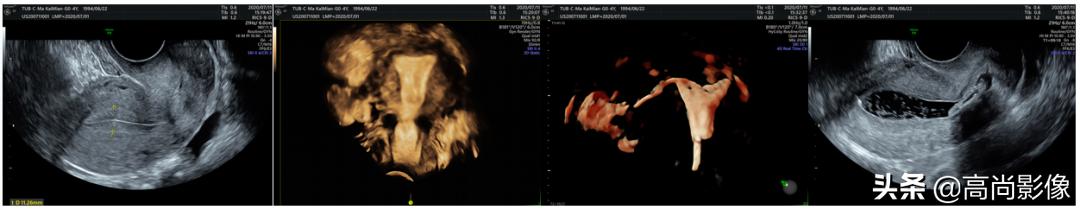

培训期间,有位外地患者慕名前来进行子宫输卵管超声造影检查。在信息科工作人员的技术指导下,程琦主任进行了检查过程的现场直播,学员们在会场观看造影图像的实时演示。